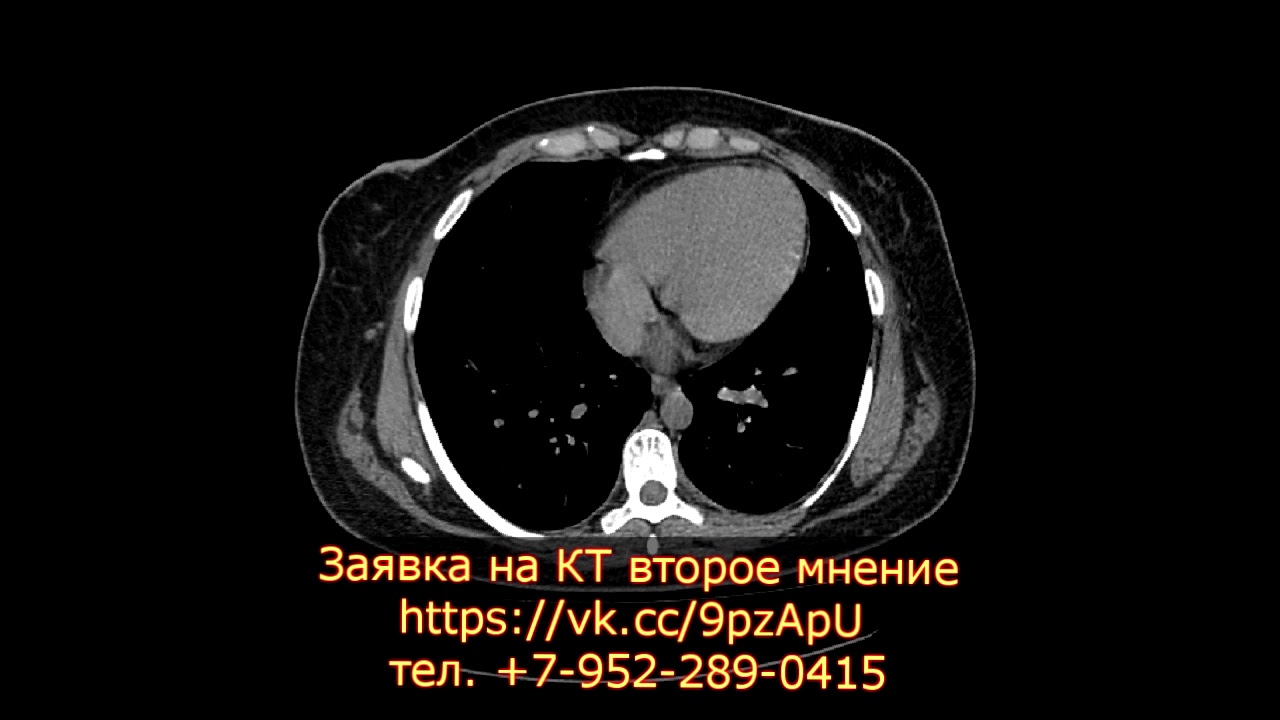

Врачи подчеркивают важность современных методов визуализации, таких как МРТ и КТ, в диагностике туберкулеза легких. Эти технологии позволяют получить детализированные изображения, что значительно улучшает точность выявления патологий. КТ, в частности, является более распространенным методом, так как обеспечивает высокую четкость изображения и позволяет обнаруживать даже мелкие изменения в легочной ткани.

Какой метод диагностики первых признаков туберкулеза легких выбрать: МРТ, КТ, рентген

Методы выбора

- Рентгенография,

- КТ.

Что покажет МСКТ и рентген грудной клетки при туберкулезе

Можно ли на КТ легких увидеть туберкулез?

С помощью КТ можно выявить практически любые изменения в бронхолегочной системе, в том числе туберкулез. К сожалению, КТ не может использоваться для скрининга заболевания (как флюорография) из-за высокой стоимости, поэтому его обычно назначают, если на ФЛГ или рентгенограмме есть патологические изменения.

Компьютерная томография считается наиболее оптимальным методом обследования органов грудной полости (выявления пневмонии, туберкулеза и прочих заболеваний). Она вообще лучше подходит для обследования полых органов, к каковым и относятся легкие, изучения состояния сосудов.

Какой снимок показывает туберкулез?

Компьютерная томография или КТ является наиболее совершенным и точным способом диагностики туберкулеза. Она позволяет получить серию послойных снимков легких, что минимизирует наложение отображений органов друг на друга, как при рентгенографии или флюорографии.